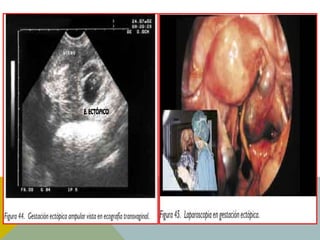

La ecografía transvaginal: es el primer paso en la exploración diagnóstica.

Nos puede dar un diagnóstico de seguridad en caso de demostrar la

presencia de saco gestacional en la trompa, con embrión y latido cardíaco.

Esto ocurre en el 5% de los casos.

El diagnóstico se confirma con laparoscopia y anatomía patológica, por lo

que se practicará en caso de duda diagnóstica.

DIAGNÓSTICO La ecografía transvaginal:es el primer paso en la exploración diagnóstica. Nos puede dar un diagnóstico de seguridad en caso de demostrar la presencia de saco gestacional en la trompa, con embrión y latido cardíaco. Esto ocurre en el 5% de los casos. El diagnóstico se confirma con laparoscopia y anatomía patológica, por lo que se practicará en caso de duda diagnóstica. La punción del fondo de saco de Douglas (culdocentesis) aunque útil, se ha abandonado por disponer de técnicas mejores La clásica demostración de decidua y ausencia de vellosidades coriales (signo de Arias-Stella) no es considerada patognomónica, pero sí altamente sospechosa. La HCG se duplica cada 2 días durante las primeras semanas del embarazo normal, llegando a un máximo hacia la 6ª-7ª semana (post-implantación). En los embarazos ectópicos la HCG crecerá más despacio de lo normal (aumenta aproximadamente un 50% en 48 horas). La HCG también nos ayuda en el diagnóstico diferencial con procesos como abdomen agudo o aborto completo.